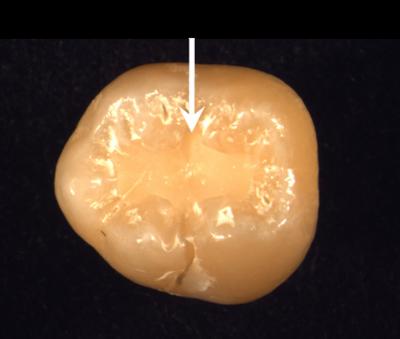

The researchers’ new technique solves a problem with the standard composite resin filling, a natural-looking restoration that is the method of choice when appearance is an issue. A dentist creates the filling by mixing the pure liquid resin with a powder that contains coloring, reinforcement and other materials, packing the resulting paste into the cavity, and illuminating the tooth with a light that causes the paste to polymerize and harden. For decay-fighting composite fillings, the problem arises from an additive that is included in the powder to provide a steady release of calcium and phosphate ions. These ions are essential to the long-term success of the filling because they not only strengthen the crystal structure of the tooth itself, but buffer it against the decay-causing acid produced by bacteria in the mouth. Yet the available ion-releasing compounds are structurally quite weak, to the point where they weaken the filling as a whole.